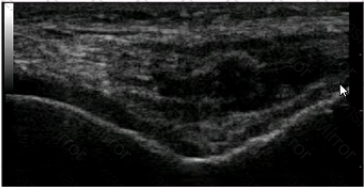

What is the BEST description for this longitudinal ultrasound scan of a 75-year-old patient with pain in the medial aspect of the knee?